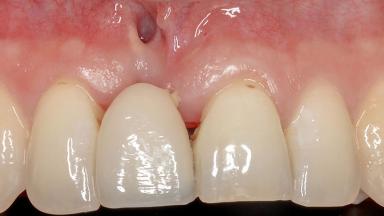

Soft-Tissue Augmentation Using a Porcine-Derived Collagen Matrix to Correct a Labial Soft-Tissue Defect Following Extraction of a Maxillary Incisor

In this case, Shakeel Shahdad employs a two-layer matrix to repair a soft-tissue defect in a post-extraction healed site prior to implant placement with simultaneous guided bone regeneration. This approach resulted in a gain of keratinized peri-implant mucosa with optimal shade and texture. Soft-tissue defects are often encountered prior to implant placement and may result in deficient attached keratinized mucosa, which unless corrected will yield less than ideal esthetic outcomes. The presence of keratinized mucosa has been proposed as one of the prognostic factors for the survival of dental implants (Adell and coworkers 1986) with reported greater reductions in gingival and plaque indices after increasing the width of keratinized mucosa by soft-tissue augmentation (Giannobile and coworkers 2018; Thoma and coworkers 2018).

Soft Tissue Contour and Volume Significantly deficient